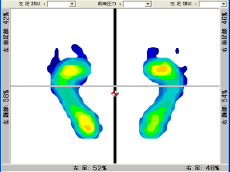

●仙骨調整による重心バランスの変化状況

(30代・男性)

1:仙骨調整前に測定

●左右バランス:左足52%、右足48%

●前後バランス:左前足部30%、左踵足70%

右前足部25%、右踵足75%

踵部に重心が傾き、足の指がほとんど写っていません。職業柄、不自然な姿勢での仕事が多く、歩く機会も少ないとのことで、男性にもこのような踵加重のタイプの方が増えています。

2:仙骨調整直後に測定

●左右バランス:左足52%、右足48%

●前後バランス:左前足部42%、左踵足58%

右前足部46%、右踵足54%

仙骨調整直後に測定しました。

両足の指も写り、前足部へ重心が移動し、バランスが改善しているのがわかります。

順次更新していきます。お楽しみに!!!